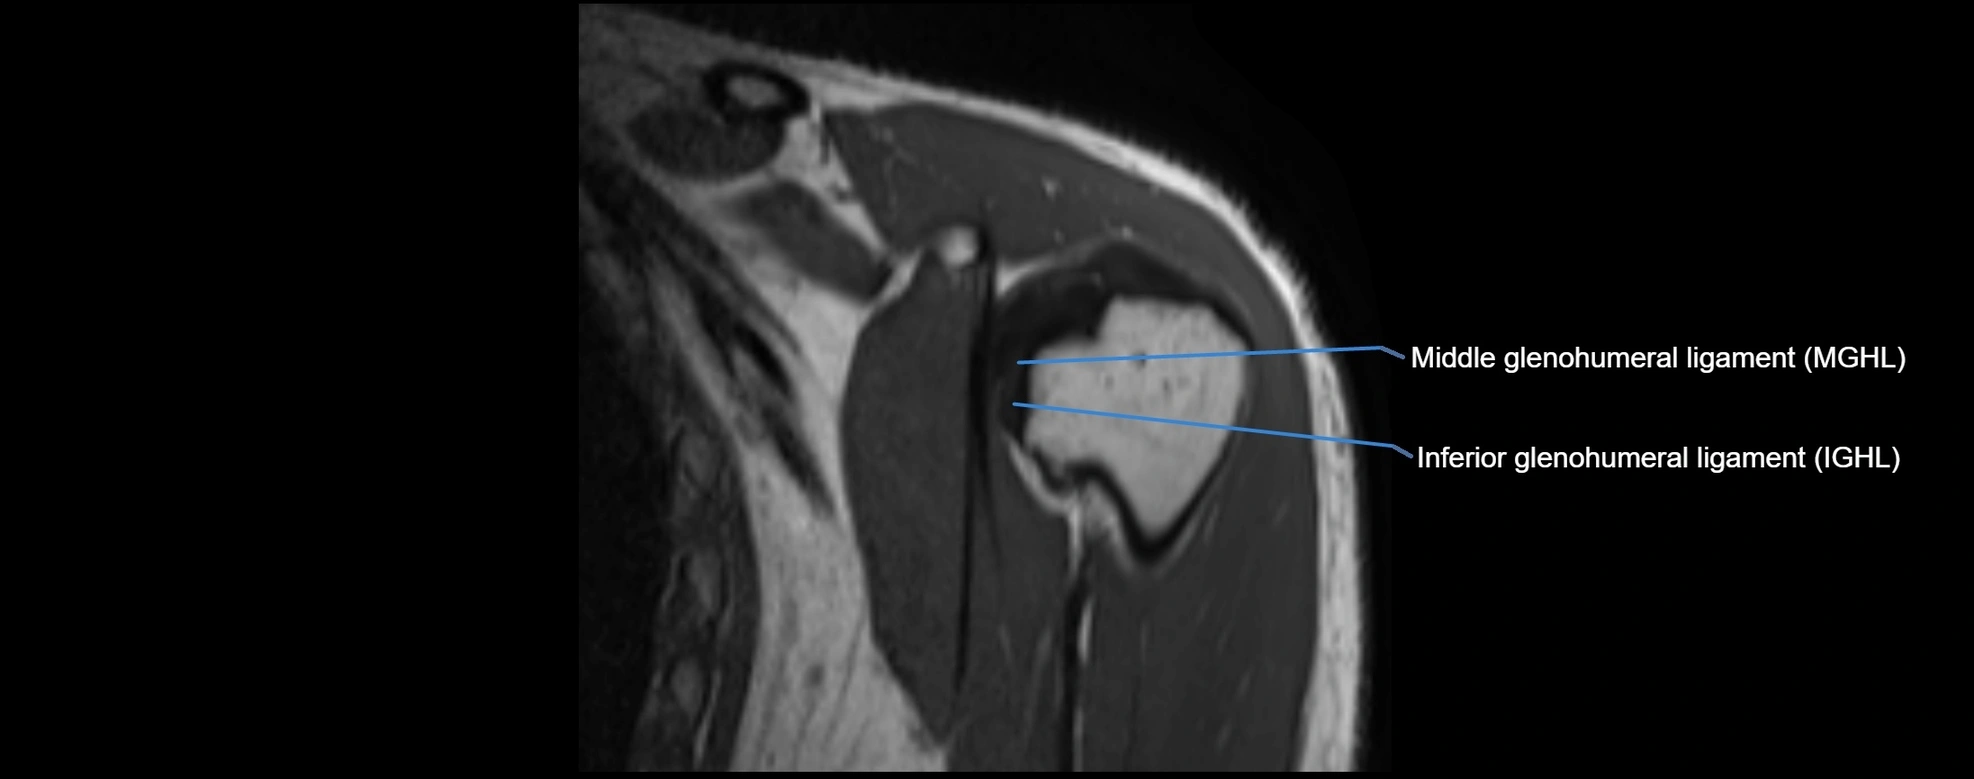

MRI images

image